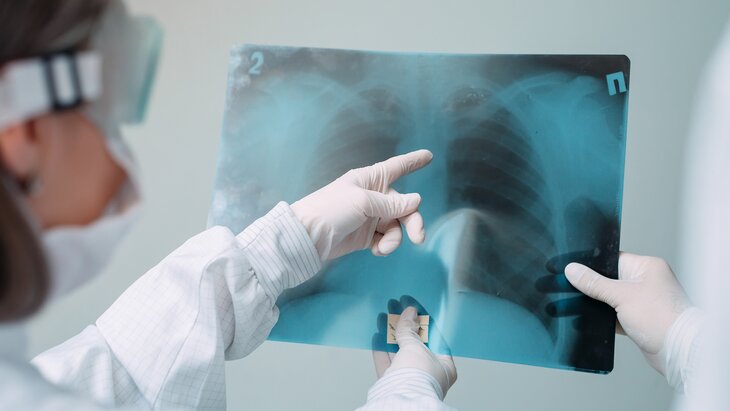

Врач Кондрахин назвал способ сохранить здоровье легких в пожилом возрасте

Отказ от курения, регулярное употребление сливочного масла и прививка от пневмонии помогут сохранить здоровье легких в пожилом возрасте. Об этом Москве 24 рассказал врач-терапевт, кандидат медицинских наук Андрей Кондрахин.

По его словам, часто пожилые имеют определенные проблемы с легкими. Чтобы держать ситуацию под контролем, нужно выполнять все рекомендации врача и принимать нужные лекарства. Кроме того, можно пройти курортное лечение – например в соляных пещерах.

"Можно также привиться от пневмонии, чтобы защититься от тяжелого течения заболевания", – добавил Кондрахин.

Врач также рекомендовал отказаться от курения, так как оно "бьет" по легким и вызывает проблемы со здоровьем.